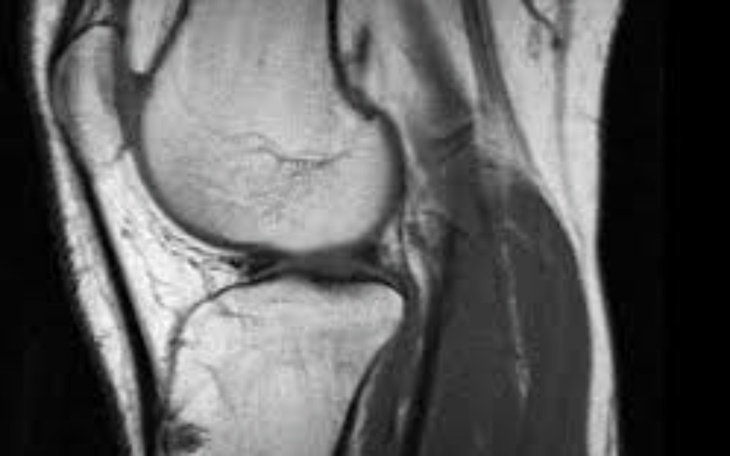

Jestem Łukasz Zbieram na operację zerwanych więzadeł mialem wypadek motocyklem i po rezonansie wyszlo ze mam zerwane więzadła krzyżowe.. Moja pasją jest motoryzacja chciałabym wsiąść jeszcze na motor caly zdrowy..